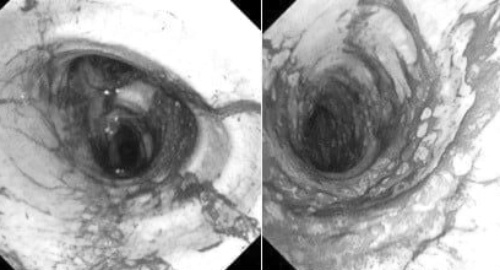

Nội soi gây mê ngày càng an toàn, nhẹ nhàng, song bác sĩ Bệnh viện Bạch Mai cảnh báo hiệu quả phát hiện tổn thương chỉ đạt tối đa khi người bệnh chuẩn bị đúng cách.